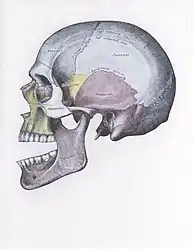

There are four different positions of jaw dislocation: posterior, anterior, superior and lateral. The most common position is anterior, while the other types are rare. Anterior dislocation shifts the lower jaw forward if the mouth excessively opens. This type of dislocation may happen bilaterally or unilaterally after yawning. The muscles that are affected during anterior jaw dislocation are the masseter and temporalis which pull up on the mandible and the lateral pterygoid which relaxes the mandibular condyle. The condyle can get locked in front of the articular eminence. Posterior dislocation is possible for people who get injured by being punched in the chin. This dislocation will push the jaw back affecting the alignment of the mandibular condyle and mastoid. The external auditory canal may be fractured. Superior dislocations occur after being punched below the mandibular ramus as the mouth remains half-open. Since great force occurs in a punch, the angle of the jaw will be forced upward moving towards the condylar head. This can result in a fracture of the glenoid fossa and displacement of the condyle into the middle cranial fossa, potentially injuring the facial and vestibulocochlear nerves and the temporal lobe. Lateral dislocations move the mandibular condyle away from the skull and are likely to happen together with jaw fractures.[4][5]

Side view of the skull with anterior dislocation of jaw.

Side view of the skull with posterior dislocation of jaw.

Side view of the skull with superior dislocation of jaw.

Front view of the skull with lateral dislocation of jaw.

The joint involved with jaw dislocation is the temporomandibular joint (TMJ). This joint is located where the mandibular condyles and the temporal bone meet.[4][6] Membranes that surround the bones help during the hinging and gliding of jaw movement. For the mouth to close it requires the following muscles: the masseter, temporalis, and medial pterygoid muscle. For the jaw to open it requires the lateral pterygoid muscle.[4]